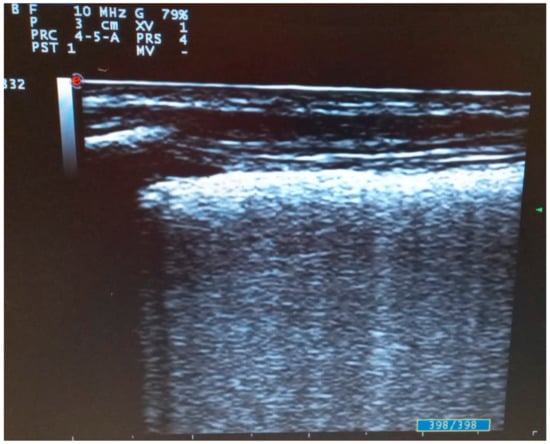

- Di Serafino, M.; Notaro, M.; Rea, G.; Iacobellis, F.; Paoli, V.D.; Acampora, C.; Ianniello, S.; Brunese, L.; Romano, L.; Vallone, G. The lung ultrasound: Facts or artifacts? In the era of COVID-19 outbreak. Radiol. Med. 2020, 125, 738–753. [Google Scholar] [CrossRef] [PubMed]